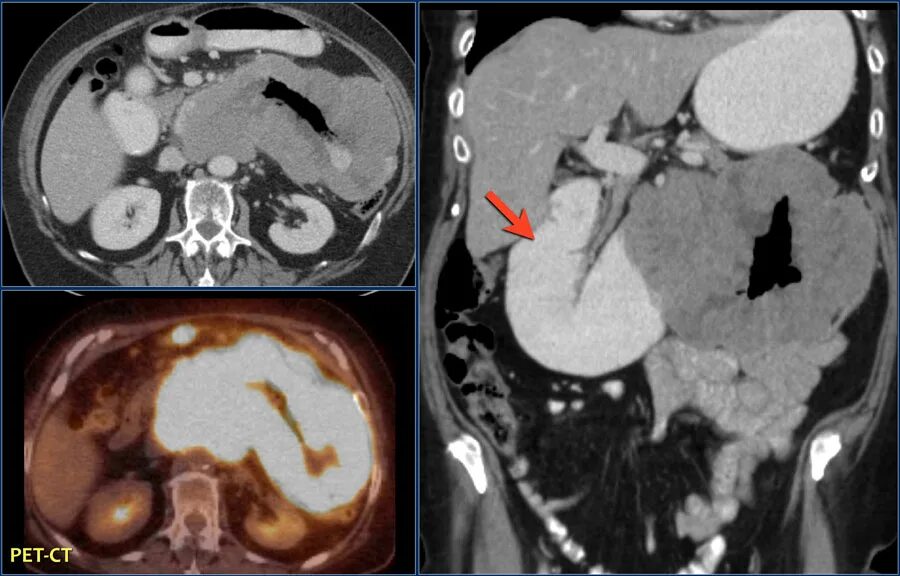

Метастазы при лимфоме